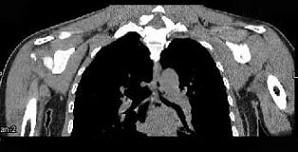

女,47岁,右肩部疼痛并肩关节活动受限数月,请结合所提供的图像,选择最佳选项 ( )A、未见明显异常B、肩周炎C、颈部肿瘤D、...

问题 女,47岁,右肩部疼痛并肩关节活动受限数月,请结合所提供的图像,选择最佳选项 ( )

选项 A、未见明显异常 B、肩周炎 C、颈部肿瘤 D、化脓性肩关节炎 E、颈椎病

答案 B